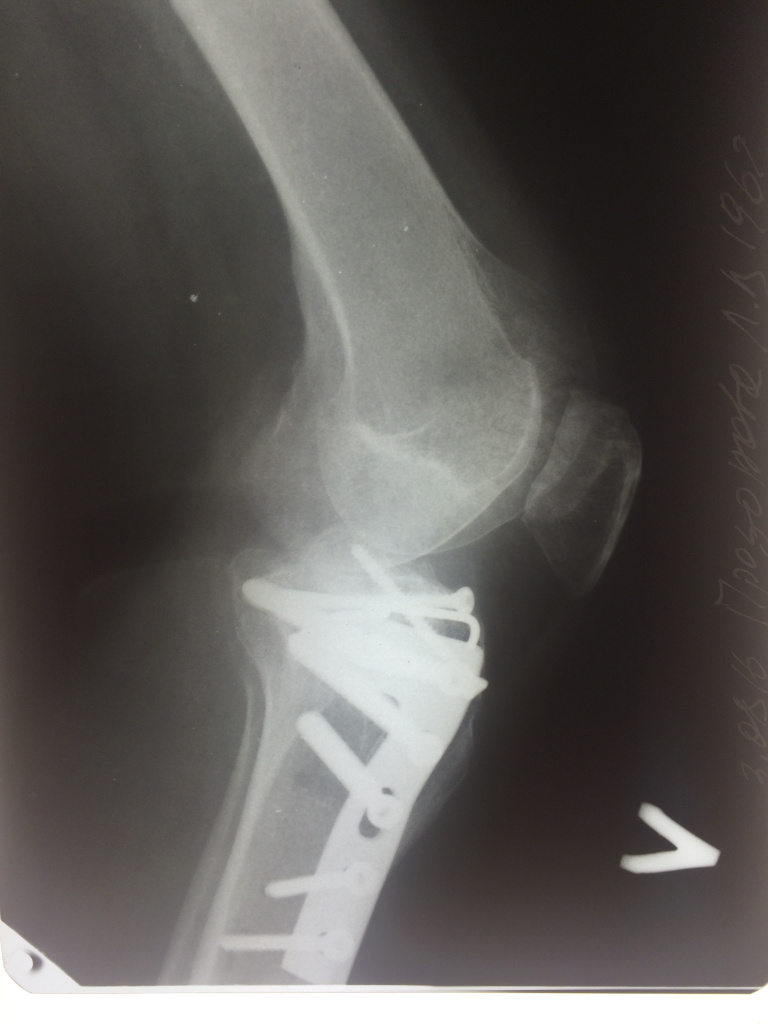

Использование материала Остеоматрикс при импрессионном оскольчатом переломе наружного мыщелка большеберцовой кости по типу Schatzker II

Использование материала Остеоматрикс при импрессионном оскольчатом переломе наружного мыщелка большеберцовой кости по типу Schatzker II.

Операция - открытая репозиция, остеосинтез большеберцовой кости опорной пластиной с костной ксенопластикой маетриалом "Остеоматрикс". На контрольных снимках в три и шесть месяцев имеется консолидация перелома, миграции фиксатора нет, имеется остеоинтеграция ксенопластического материала. Функция коленного сустава полная.